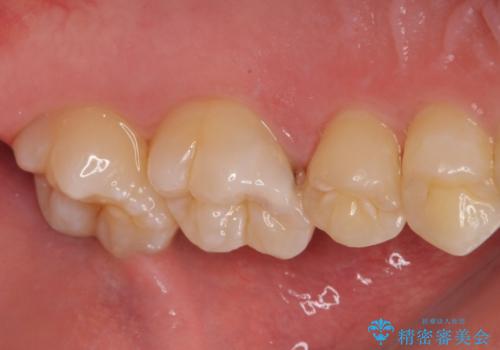

歯に穴が開いた セラミックインレー修復

- 当院でインビザラインによる矯正治療が終わった患者様です。

矯正治療終了時歯に穴が開いたとのことで、治療を希望されました。

拡大鏡視野化にて、虫歯を除去し、セラミックインレー(セラミックの詰め物)に適した形に整えました。

セラミックインレー装着時には、ラバーダム防湿にて装着をしています。